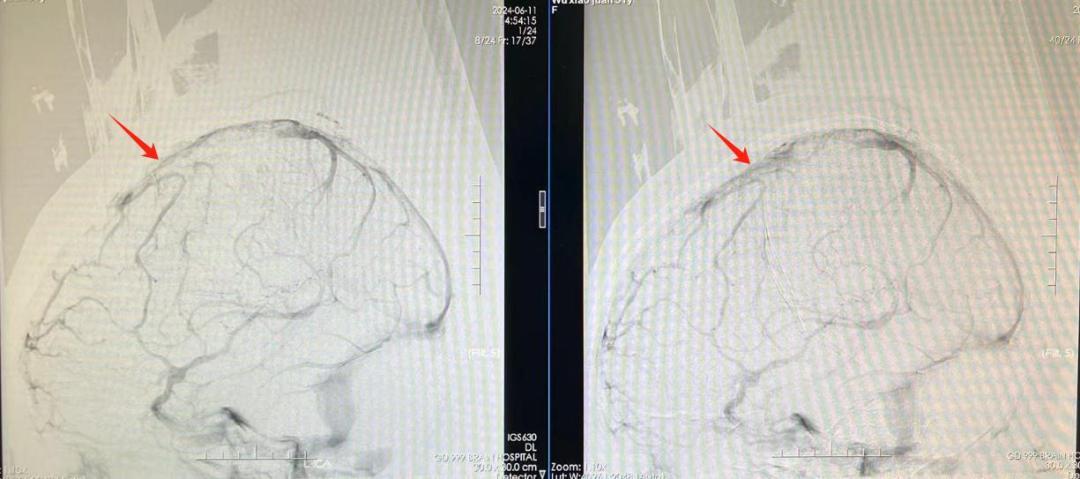

随后,医生紧急将堵塞在患者静脉窦内的栓子取出,再应用抗凝血药物进一步稳定病情。“静脉血管通畅后,颅压下降,患者颅内的血块有望自行吸收,无需再行开颅手术。”神经外十科冯桂栗主治医师补充道。目前,小莫已恢复清醒,能够对话、吃饭,正在接受进一步康复治疗。

取栓前:静脉窦显影不佳(左);取栓后:静脉窦显影好转(右)